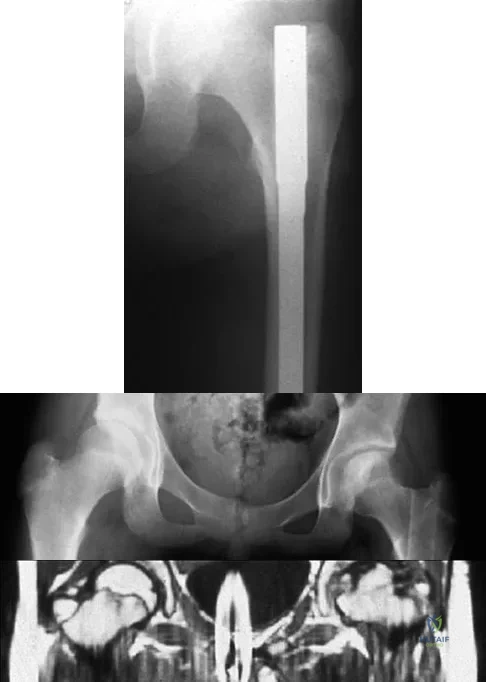

A 38-year-old woman with metastatic thyroid carcinoma has had increasing pain in the left hip for the past 3 months. An AP radiograph and coronal T1-weighted MRI scan are shown in Figures 28a and 28b. Management should consist of

Correct Answer: cemented bipolar hemiarthroplasty.

Explanation:

The radiograph and MRI scan reveal a lytic lesion in the left femoral neck region that extends to the lesser trochanter. Although external beam radiation and radioactive iodine infusion may be helpful in controlling the local disease, the patient is at high risk for femoral neck fracture given the location of the lesion. Prophylactic surgery is indicated; therefore, the treatment of choice is a cemented bipolar hemiarthroplasty. The use of a compression hip screw and side plate or an intramedullary nail has a high likelihood of failure with disease progression. Postoperative treatment with radiation therapy and bisphosphonates is also indicated. Mirels H: Metastatic disease in long bones: A proposed scoring system for diagnosing impending pathologic fractures. Clin Orthop 1989;249:256-264. Swanson KC, Pritchard DJ, Sim FH: Surgical treatment of metastatic disease of the femur. J Am Acad Orthop Surg 2000;8:56-65.